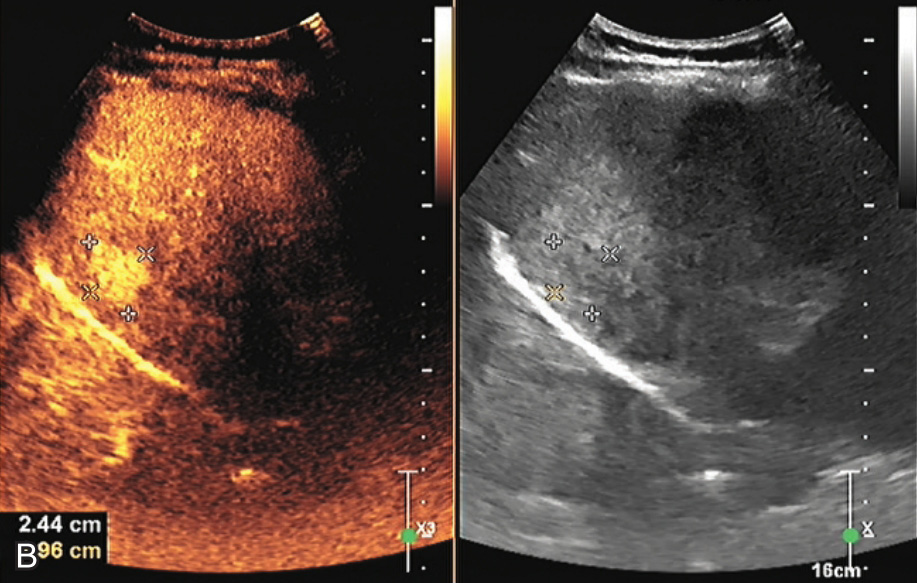

图1-5-2 肝细胞腺瘤超声造影图像

A.动脉期病变快速增强,病灶周边有灌注的环状高回声并伸入病灶内部

图1-5-2(续)

B.门脉期始终呈高增强;C.延迟期始终呈高增强